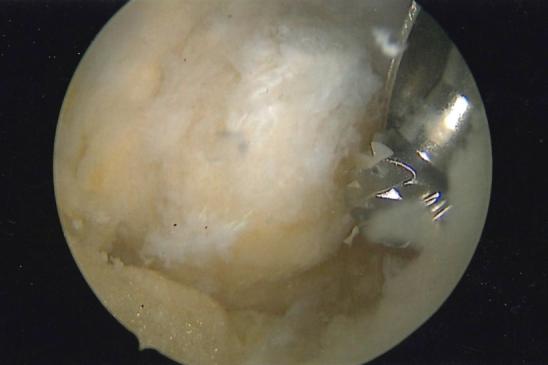

Arthroscopic resection of symptomatic unfused tibial tubercle ossicles causing chronic anterior knee pain due to recalcitrant Osgood-Schlatter disease has been shown to be a reproducible arthroscopic technique. Although a number of other surgical techniques have been described, including ossicle excision and tubercle-plasty, drilling of the tibial tubercle, bone peg insertion to induce fusion, open excision of loose fragments, direct bursoscopic ossicle resection, and closing-wedge tubercle osteotomy, with varied outcomes, this technique offers a minimally invasive approach with low risk. Complications including injury to the patellar tendon and scarring of the anterior fat pad have been previously reported, but this approach can be performed with minimal fat pad debridement and direct visualization of the patellar tendon during all resections. This article presents a technique for arthroscopic resection and debridement of unfused ossicles in patients with chronic anterior knee pain due to Osgood-Schlatter disease by use of minimally invasive arthroscopic techniques that are used in standard knee arthroscopy and should be familiar to most arthroscopists.

对于因难治性胫骨结节骨软骨炎导致慢性前膝痛的有症状未融合胫骨结节小骨,关节镜下切除已被证明是一种可重复的关节镜技术。尽管已经描述了许多其他手术技术,包括小骨切除和结节成形术、胫骨结节钻孔、插入骨栓诱导融合、开放切除游离碎片、直接关节镜下小骨切除以及闭合楔形结节截骨术,且结果各异,但该技术提供了一种微创方法,风险较低。先前已报道过包括髌腱损伤和前脂肪垫瘢痕形成等并发症,但这种方法在所有切除过程中可通过最小限度的脂肪垫清创和直接观察髌腱来实施。本文介绍了一种通过使用标准膝关节镜检查中使用的微创关节镜技术,对因胫骨结节骨软骨炎导致慢性前膝痛的患者进行关节镜下未融合小骨切除和清创的技术,大多数关节镜医生应该熟悉这些技术。